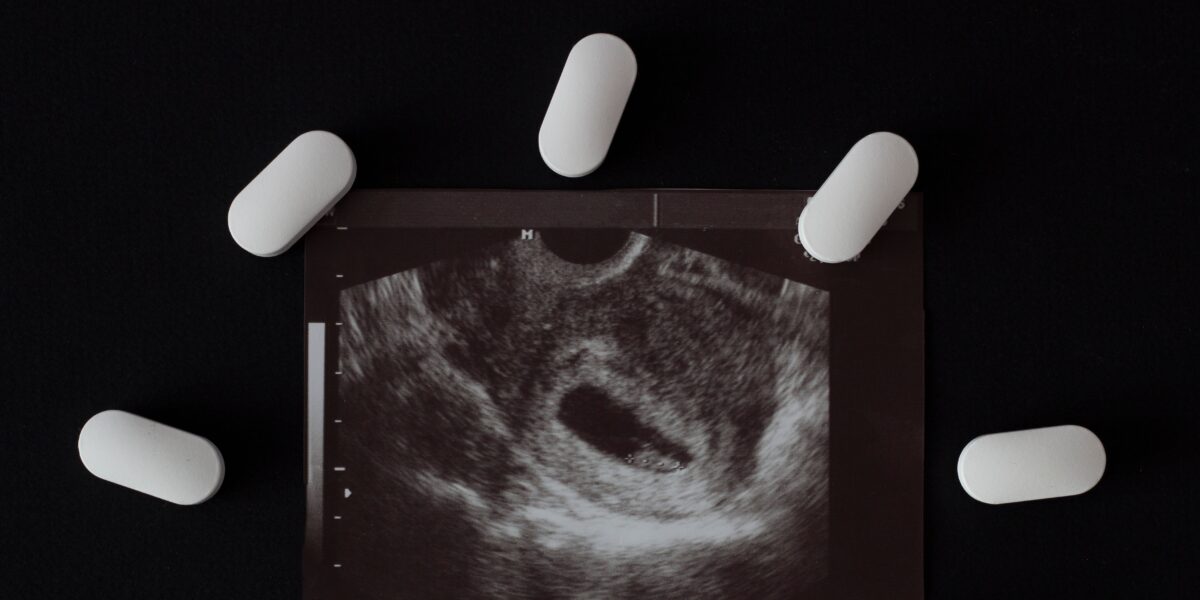

The fight against abortion’s normalization in healthcare is far from over. ACOG continues to expand its abortion training initiatives, enlisting not just OB-GYNs but also Family Medicine (FM) and Internal Medicine (IM) doctors, midwives, nurse practitioners, and even pharmacists to prescribe abortion pills through new pilot programs.

In December 2024, California committed $18 million to accelerate abortion training through the Reproductive Health Care Access Initiative. This funding extends beyond OB-GYNs, including physician assistants (PAs) and other practitioners. Medical abortion—using pills rather than surgical procedures—has opened the door for doctors without specialized reproductive care training to provide abortions. Additionally, the University of Illinois College of Nursing was one of three organizations chosen to receive $2 million in funding from the state’s public health department to enhance abortion training programs.